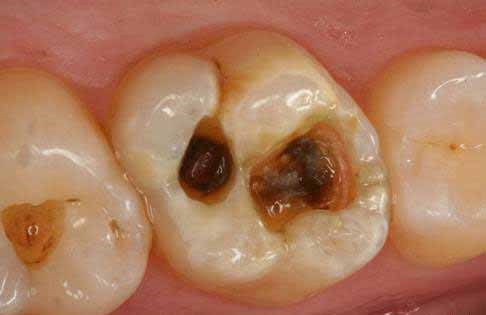

- 🔹 Định nghĩa: Viêm tủy răng xảy ra khi vi khuẩn phá vỡ cấu trúc răng và xâm nhập vào tủy.

- ⚡ Tủy viêm do lỗ sâu lớn hoặc răng nứt

- Khi vi khuẩn xâm nhập sâu vào tủy qua lỗ sâu hoặc vết nứt, tủy bị kích thích mạnh, áp lực trong tủy tăng, gây đau nhức dữ dội, đau nhói. Cơn đau thường tăng lên khi ăn, nhai, hoặc tiếp xúc thức ăn nóng/lạnh, và không giảm khi dùng thuốc giảm đau thông thường. Đây là lúc bạn cần điều trị tủy chuyên sâu tại nha khoa để loại bỏ vi khuẩn, giảm đau và bảo tồn răng.

- ✨ Chăm sóc và vệ sinh răng miệng chưa đúng tiêu chuẩn

- Việc bỏ qua đánh răng định kỳ hoặc chải răng sai kỹ thuật sẽ tạo điều kiện cho vi khuẩn phát triển âm thầm. Khi vi khuẩn xâm nhập qua men răng và ngà răng, tủy răng trở thành mục tiêu tổn thương, dẫn đến viêm tủy và các biến chứng nghiêm trọng.